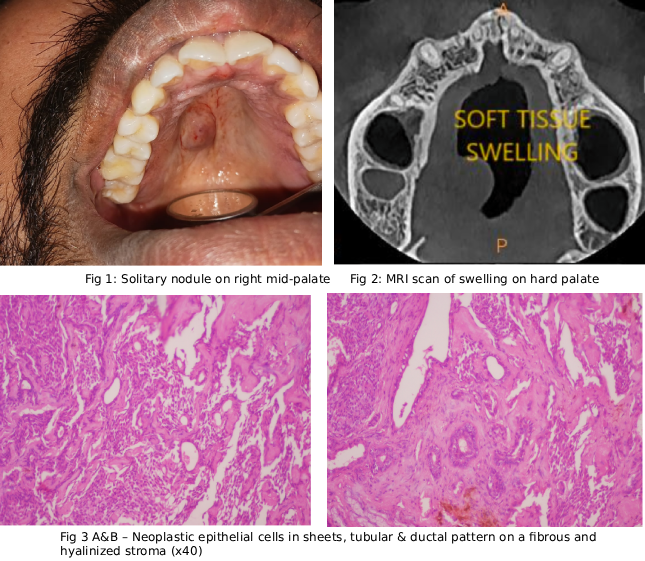

Case Study 2

Final Diagnosis: ORAL SQUAMOUS CELL CARCINOMA OF PALATE (Moderately differentiated)